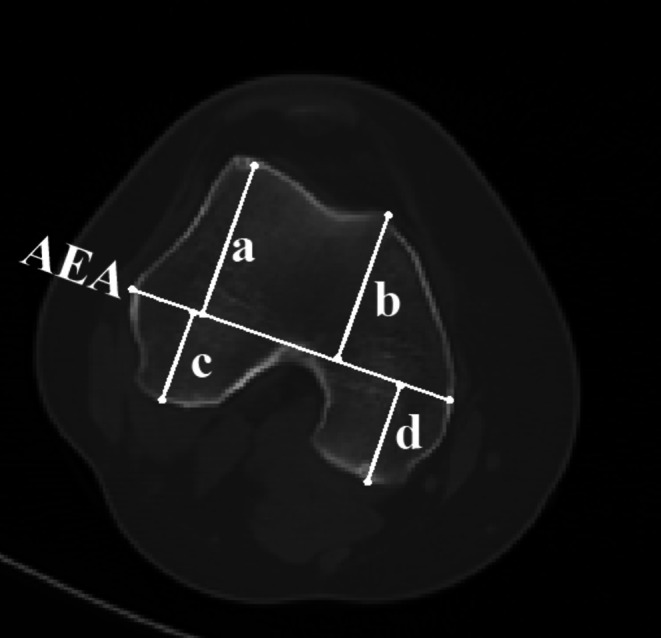

Methods: Sixty-seven patients (10 male and 57 female) with unilateral DDH in our center between May 2019 and March 2024 were retrospectively analyzed. Then, the lengths of each part of the femoral condyle were collected from CT, and the ratios of anterolateral condyle to anteromedial condyle (ALC/AMC), posterolateral condyle to posteromedial condyle (PLC/PMC), lateral condyle to medial condyle (LC/MC), anterolateral condyle to posterolateral condyle (ALC/PLC) and anteromedial condyle to posteromedial condyle (AMC/PMC) were calculated. Then, the patients were grouped by Crowe classification to further analyze the morphology of the distal femur condyle. The mechanical axis deviation (MAD) of the lower limbs was evaluated. The Pearson correlation coefficient was used to explore the correlation between knee valgus and the morphology of the femur condyle.